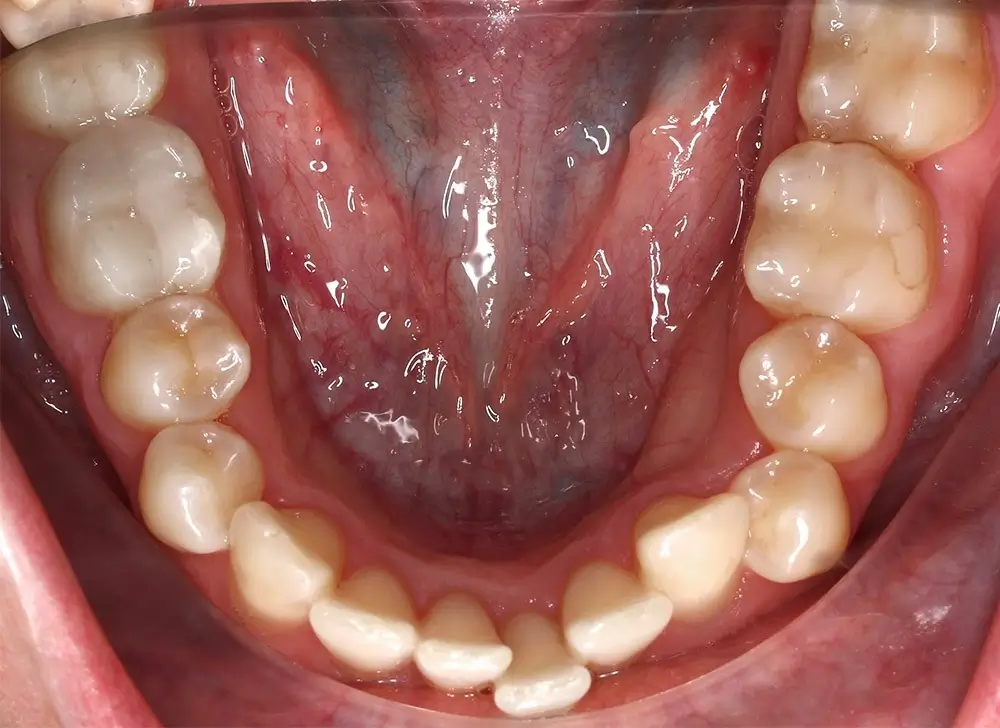

Кейс 13

Булгач (Мочалова) Галина Игоревна

Количество кап ВЧ 19

Количество кап НЧ 24

ДО

ПОСЛЕ